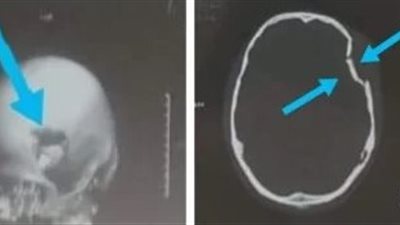

نجح فريق جراحي بقسم جراحة المخ والأعصاب بمستشفي كفر شكر التخصصي بمحافظة القليوبية، في إنقاذ حياة شاب